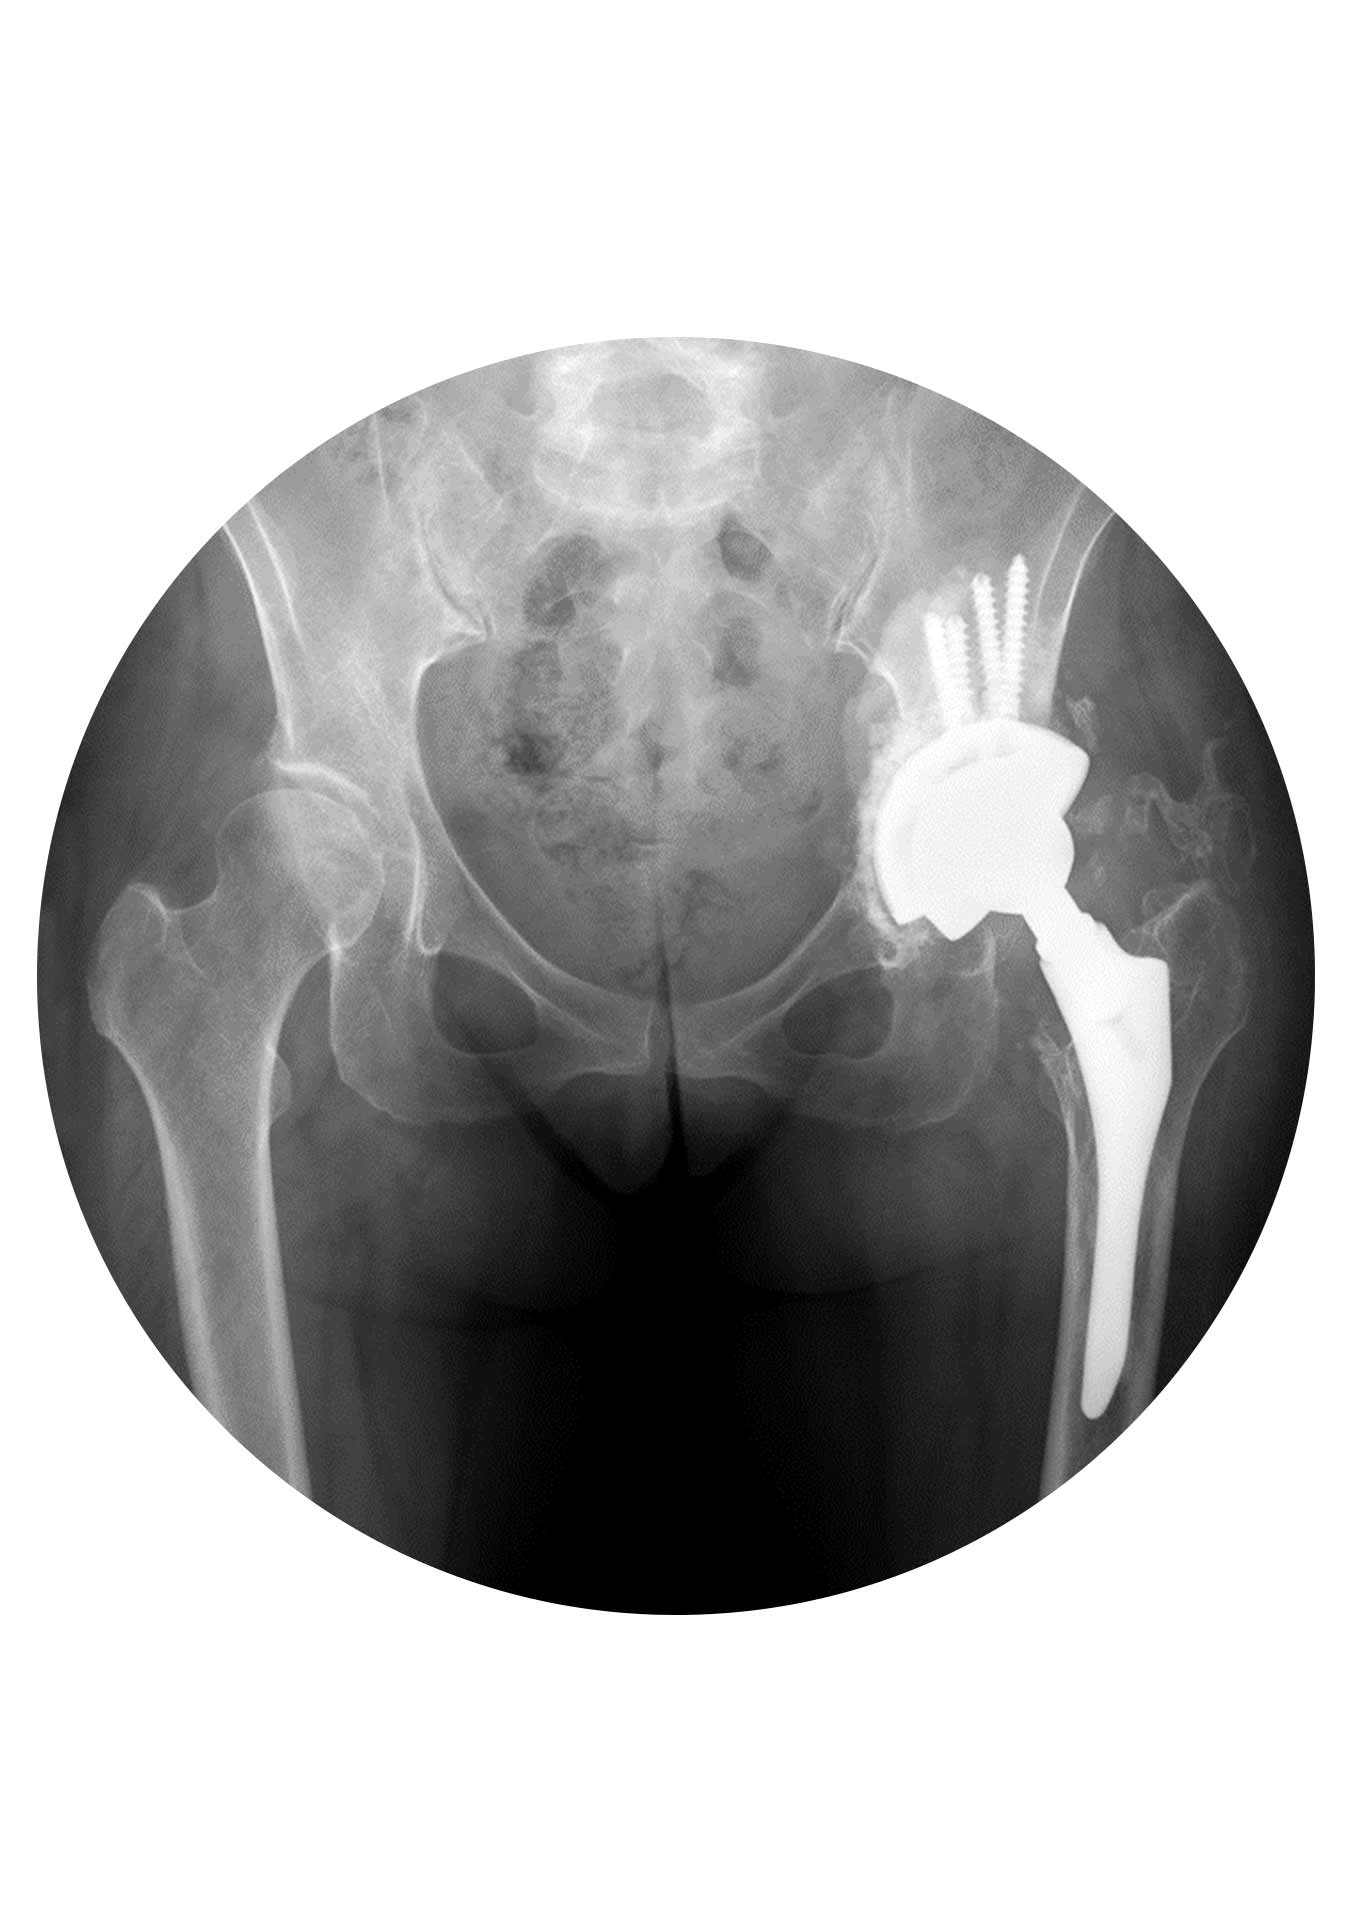

O objetivo dessa cirurgia é corrigir o problema para que a anca volte a funcionar normalmente outra vez. O principal obstáculo e desafio destas cirurgias é a “falta de osso”, ou seja, a destruição óssea quer pela causa da falência quer pela remoção dos implantes no momento da revisão. A sua complexidade varia muito dependendo da causa da falência e pode ir desde a simples substituição de um “plástico gasto” (polietileno) até à remoção total da prótese e substituição por outra (no mesmo tempo cirúrgico ou algumas semanas após) no caso de uma infeção.

Segundo: reconstrução da “nova” articulação. Embora o momento da remoção dos implantes seja importante no resultado da cirurgia de revisão, esta é na sua essência uma cirurgia de reconstrução.

Em relação ao material disponível (ao contrário da prótese primária) ele é extremamente variado e complexo… dividindo-se de uma forma simplista em material de reconstrução acetabular (redes, cages, cups multi-furos, aumentos e batentes) e material de reconstrução femoral (hastes modulares, hastes tipo Wagner, hastes com fixação distal, placas trocantéricas e cabos de aço)… até material customizado (implantes produzidos especificamente para cada caso).